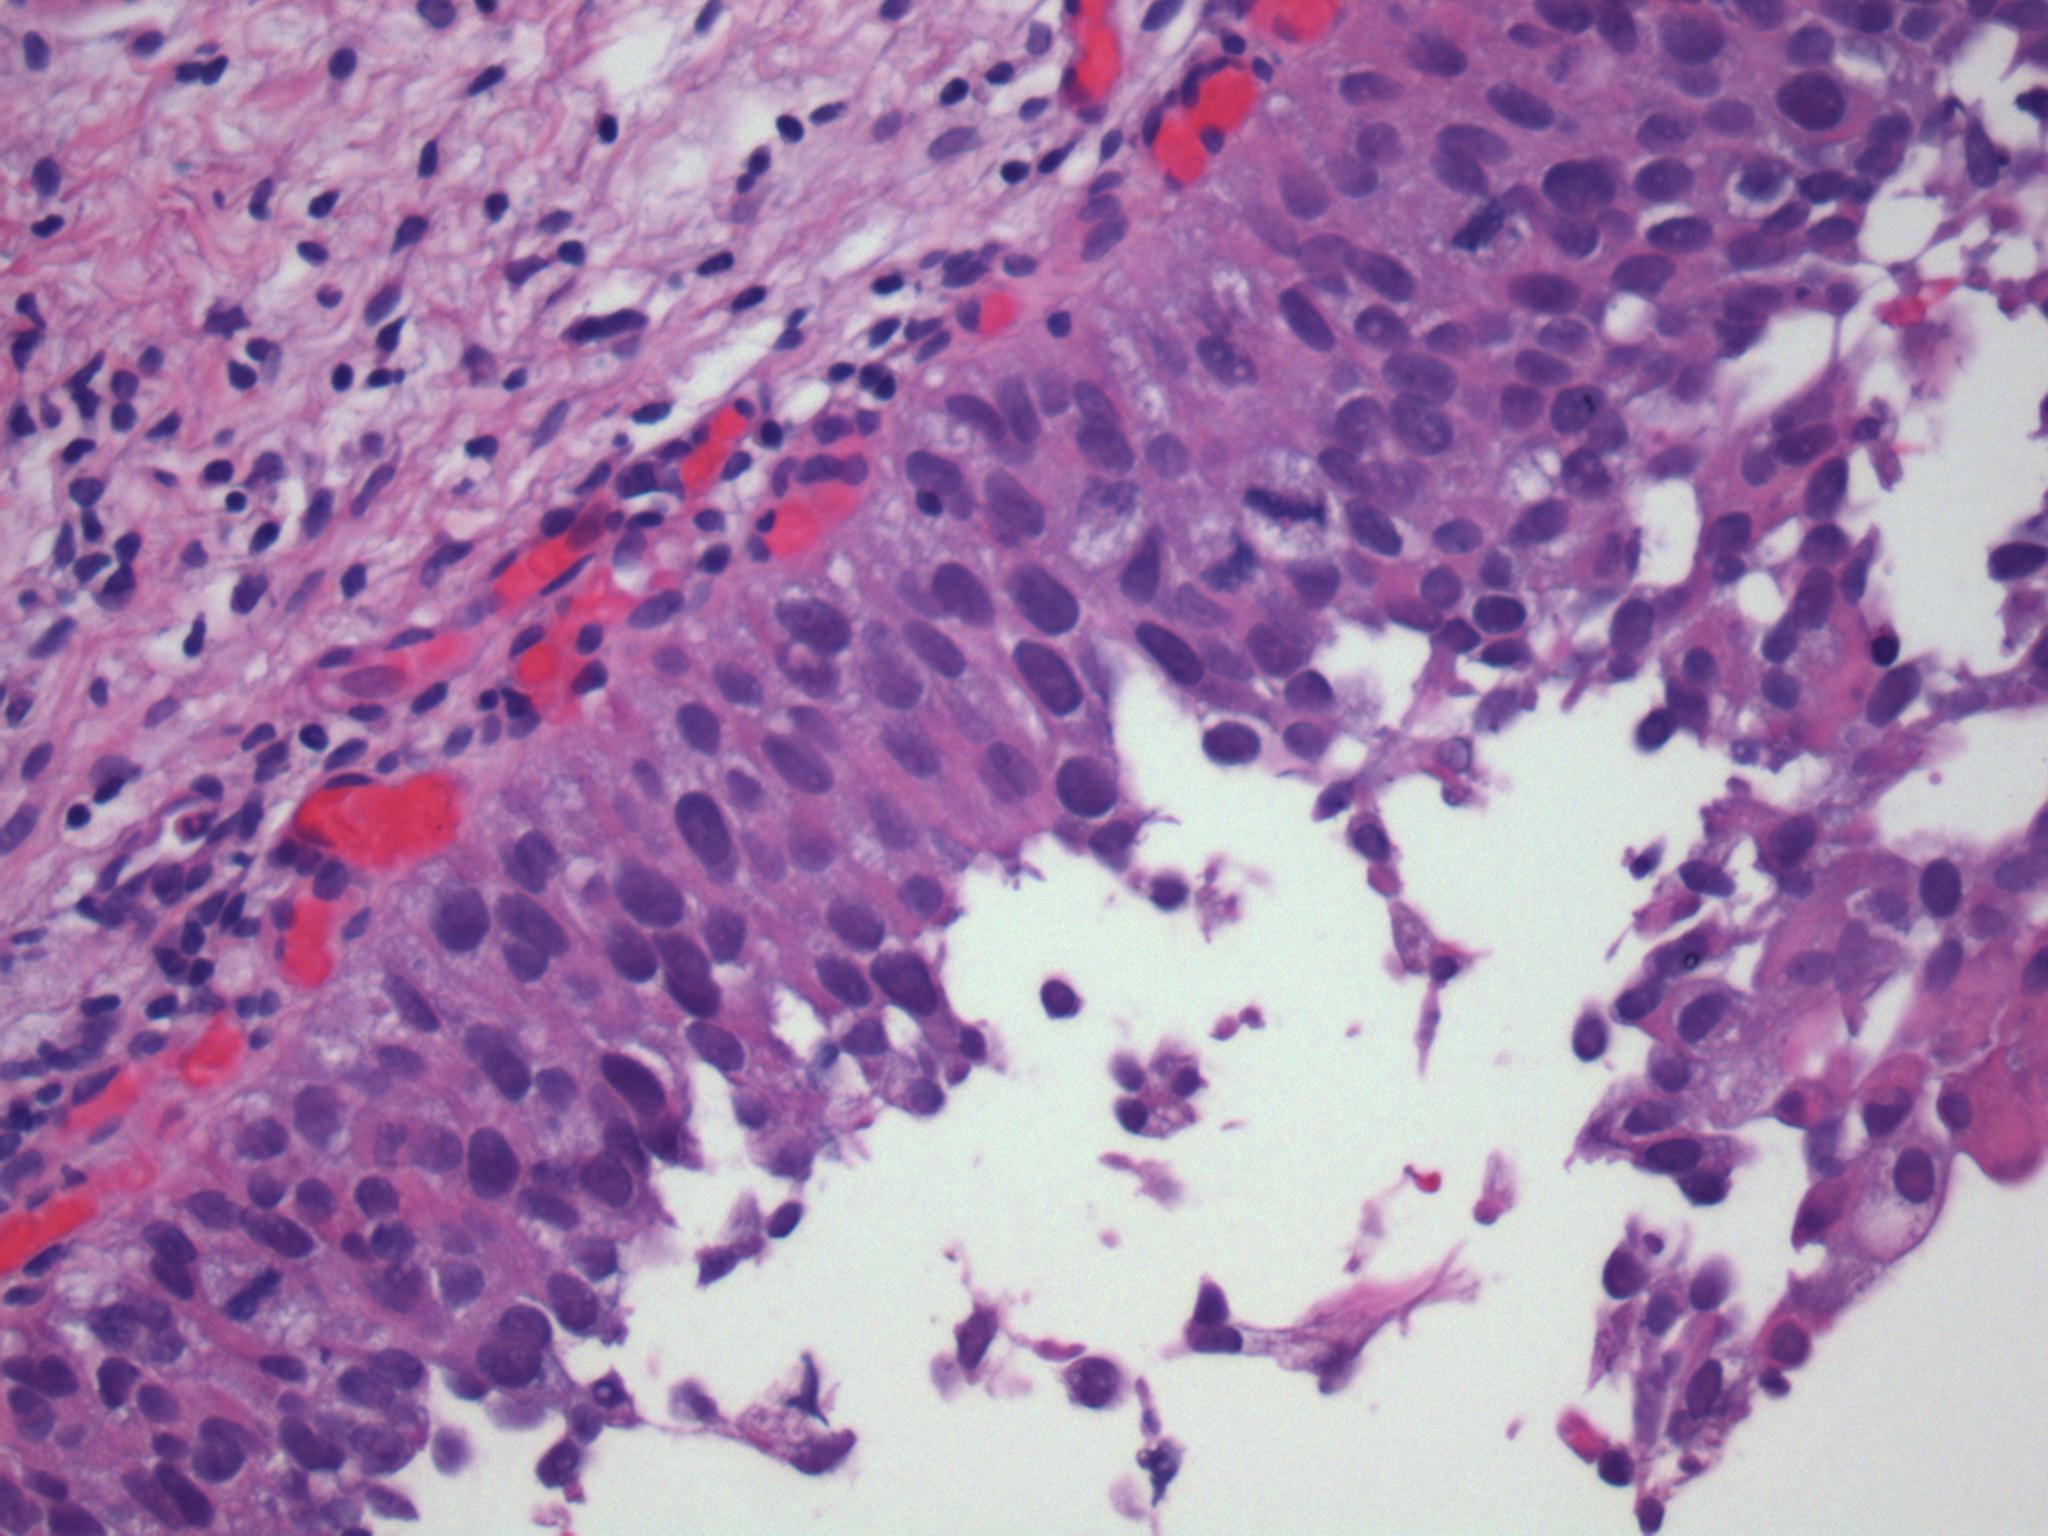

Consensus grade: Carcinoma in situ (CIS)

The urothelium displays loss of cohesion, loss of polarity and prominent pleomorphism.